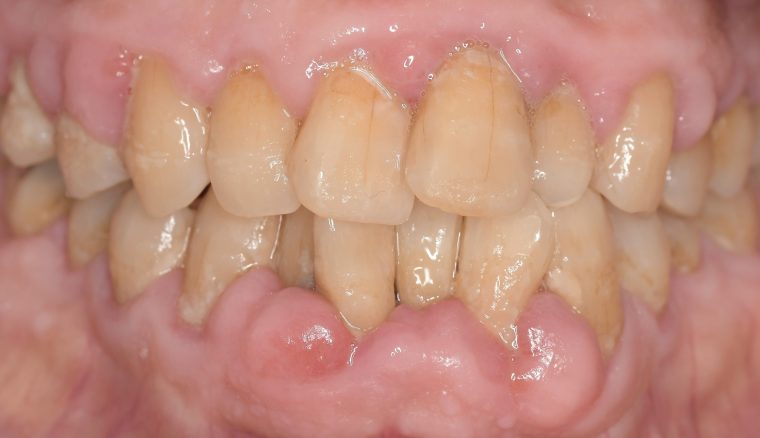

CASE 4

Before

After

基本情報

| 年齢・性別 | 52歳・女性 |

|---|---|

| 主訴 | クリーニングしたい |

| 治療内容 | スケーリング・PMTC |

| 治療期間 | 60分 |

| 治療費 | 約7,000円 |

| リスク・副作用 | 知覚過敏、歯肉退縮 |

| 治療方針 | 歯石とステインを除去して、今後は定期検診でのクリーニングと併せてガムピーリングやホワイトニングを行います。 |

| 担当者所見 | 歯肉の色素沈着が目立つため、ガムピーリングを行いながらホワイトニングを行うことをおすすめします。 |